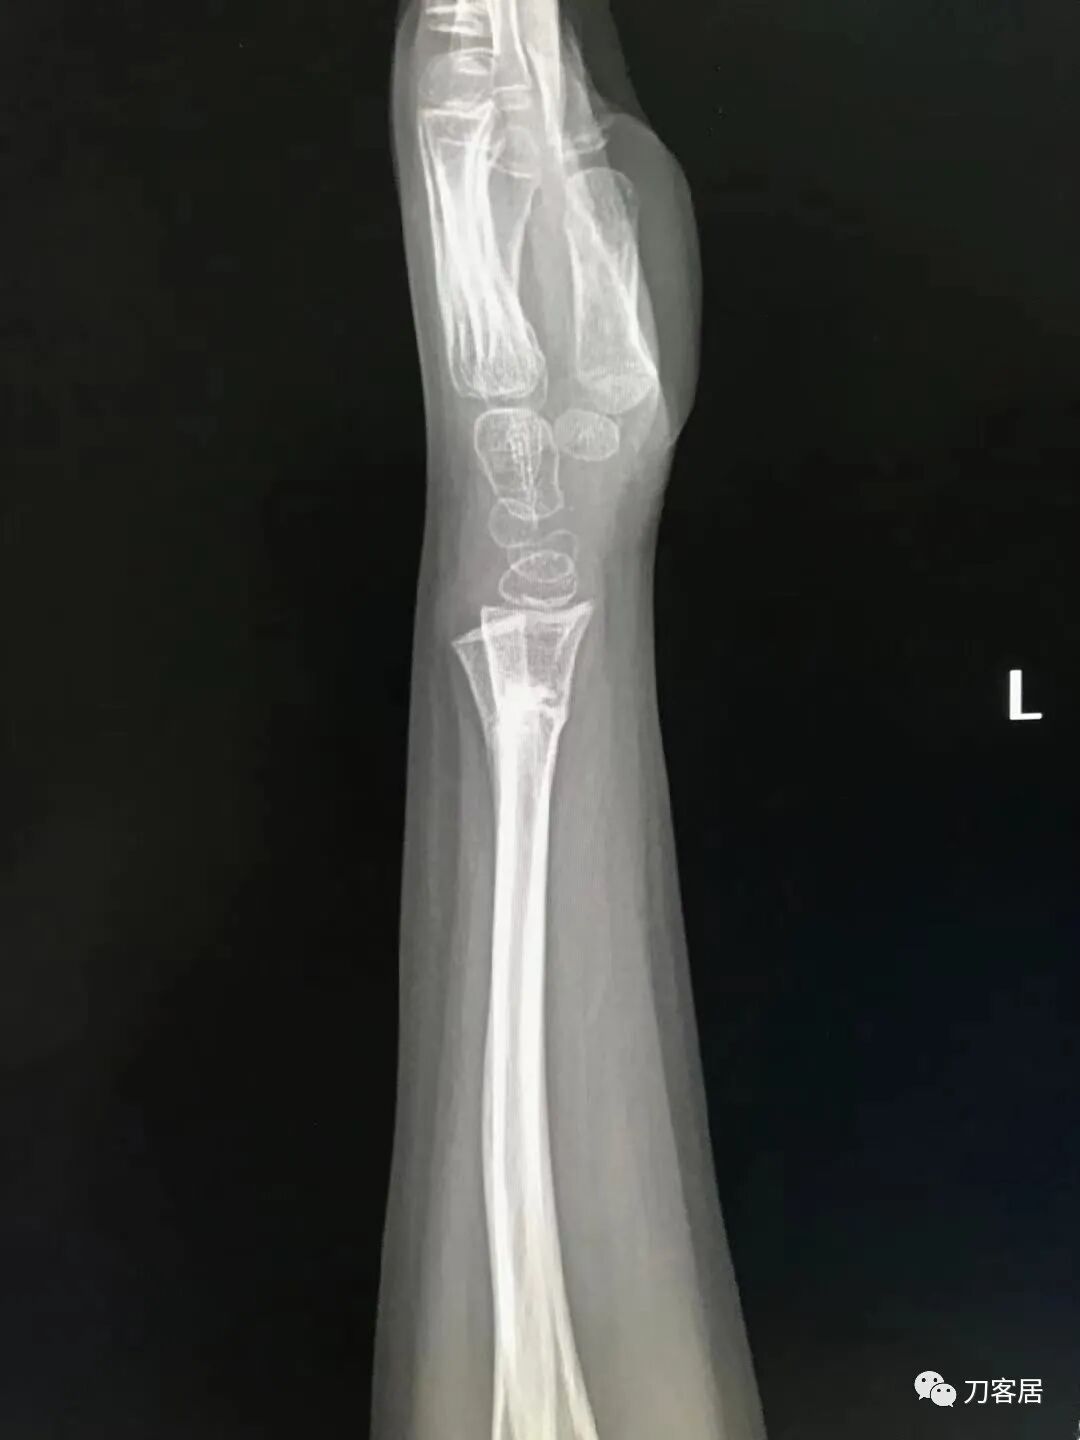

下面是这个6岁孩子,尺桡骨远端双骨折的术前及术后片子和外观照片。

1.  这是一个很简单的6岁儿童无移位的尺桡骨远端骨折。没有皮肤损伤,没有移位,没有骨折碎块儿。

2.  这个骨折处理起来也很简单,单纯的打石膏托或者中医的小夹板,或者正规的包括腕关节和肘关节的管型石膏外固定4周即可治愈该骨折。实在不行,如果这个孩子比较听话,不太调皮的话,用一本书,一个三角巾悬吊固定4周,都可以治愈该骨折。但是给这个患者用外固定架做了手术,而且桡骨远端的几颗克氏针距离骨折线太近,其中一枚克氏针进入到骨折间隙内。从这个术中图片来看,术者的外固定手术技术也有待于进一步的提高。毕竟术者应该还很年轻。从X线片来看,前臂及手的尺侧有不透光影,应该还使用了外固定石膏绷带托,而且我猜测应该是高分子的石膏绷带托,这个是纯属猜测,不一定是对的,不过如何解释前臂尺侧的不透光影呢?如果真是用了石膏绷带外固定的话,那为啥要做手术呢?外固定架术后就不该再用石膏绷带托辅助了。

3.  对于肢体骨折,特别是前臂长骨骨折,双骨折虽然不稳,但更容易手法复位,往往单骨折手法复位比较困难。该病例患儿6岁,尺桡骨双骨折,没有移位,所以根本就不存在需要复位的,直接打石膏外固定即可。孩子年龄越小,塑形能力越强,愈合速度越快,即使是有轻度的畸形骨愈合,在未来的塑形过程中,自然而然的恢复正常的力线和功能。对于该病例,即使是不干预,再过1-2周,只要骨折断端不移位,也能正常愈合而不留任何畸形。